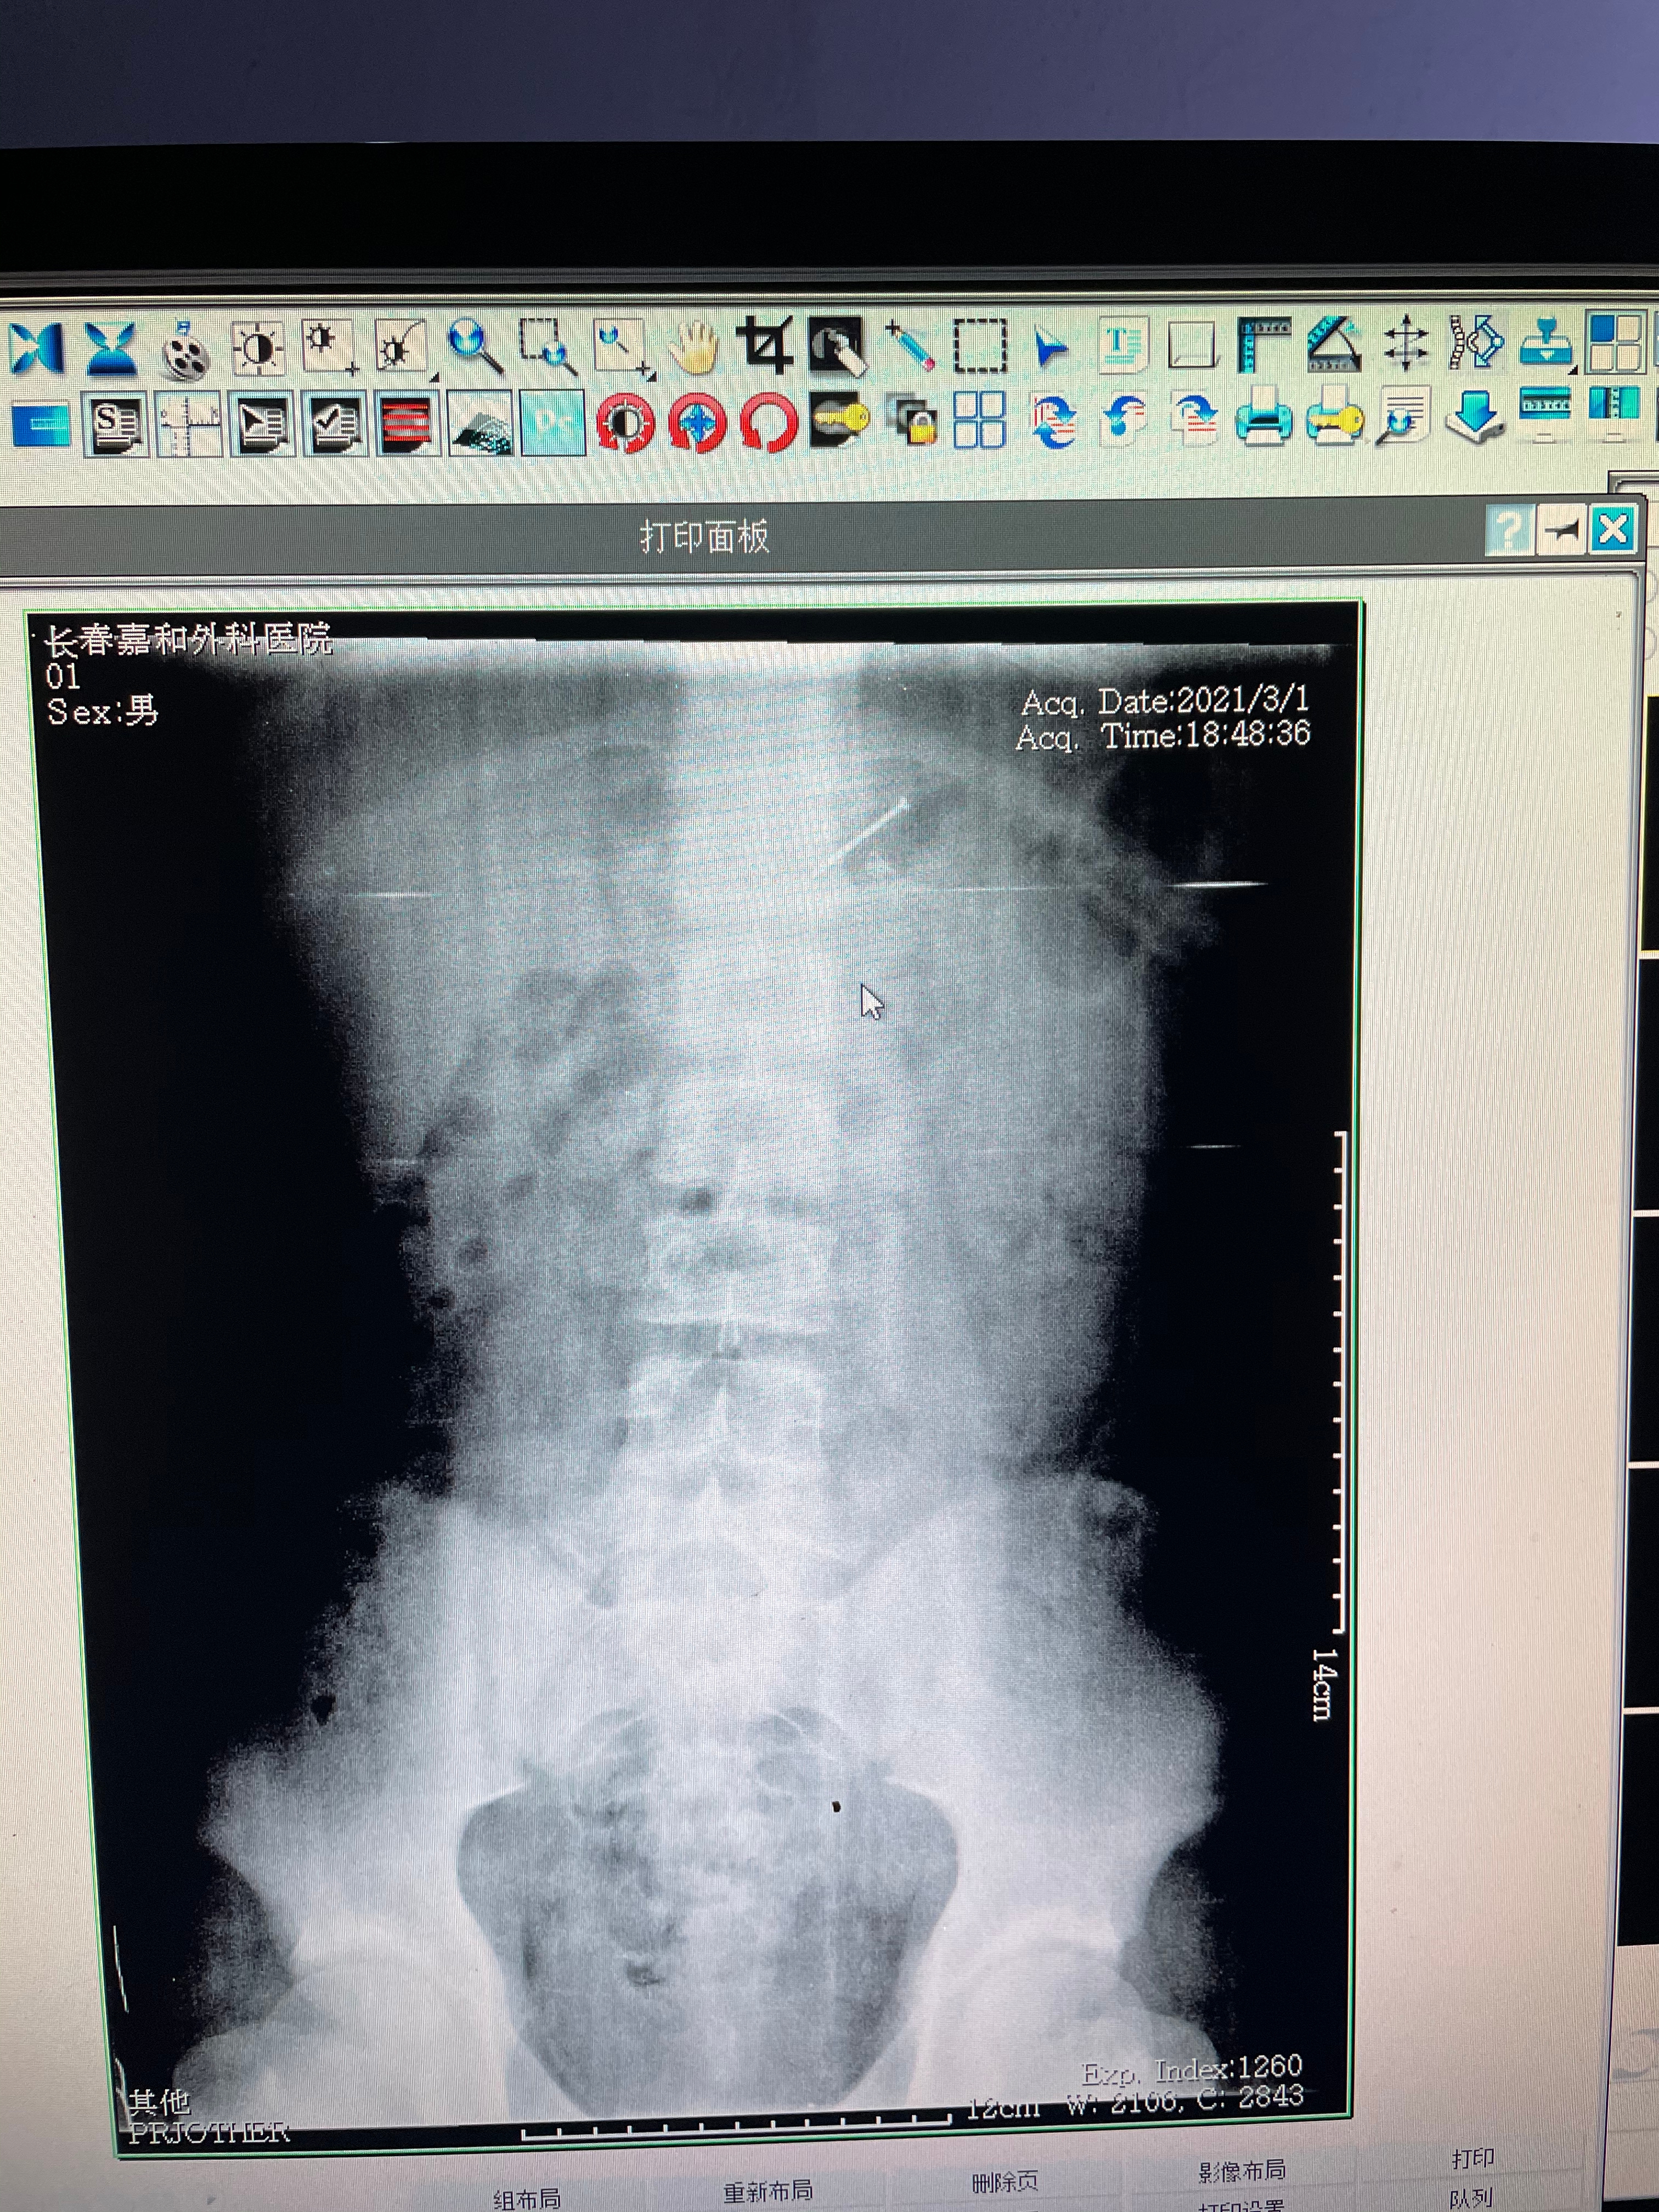

医院的医生得知情况后,马上为患者开辟了绿色通道,安排男孩拍片检查。晚6时51分便拍完了片子,随后又迅速制定周密的取出方案,晚7时许开始取出工作,此时,钢钉已进入到胃腔内,医生决定经胃镜下取出。晚7时10分,男孩体内的钢钉被成功取出。

医生在对其胃镜检查时,以为男孩胃腔内的钢钉约2厘米左右,可是取出时才发现,这根钢钉足足有4厘米长,而且十分尖锐。医生表示,这样的情况是十分危急的,取出过程中,如果钢钉掉入气管内后果不堪设想,甚至可以危及生命。男孩体内的钢钉被取出不久后,他便在家人的带领下离开医院返回家中。